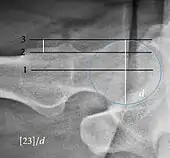

| Caput-sourcil angle[21] | ![]() |

Superior to the Tönnis angle in cases without joint space narrowing or subluxation.[21] The medial point of the sourcil is at the same height as the most superior point of caput femoris. | −6 to 12°[21]

|